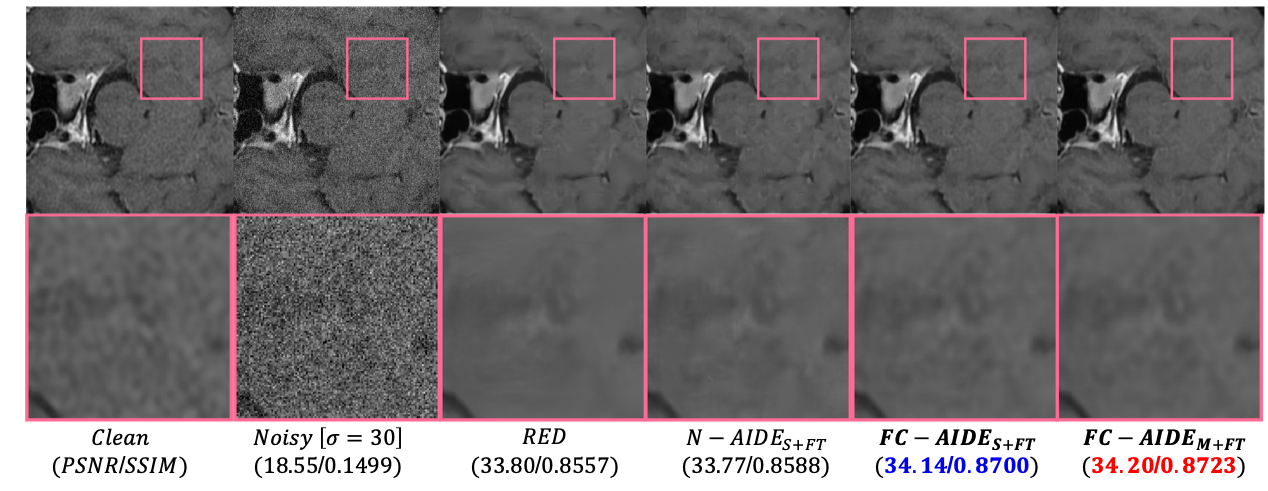

6 Visualization

Figure 10 and 11 show the clean images used for Set5 and Set12. Moreover, in Figures 6∼similar-to\sim9, we visualized the denoising results on sample images from our evaluation datasets, i.e., Set12, BSD68, Urban100, Manga109, BSD68/Laplacian and Medical/Gaussian. We compare our FC-AIDES+FTS+FT{}_{\texttt{S+FT}} with the most competitive state-of-the-art baselines and show the superiority of FC-AIDES+FTS+FT{}_{\texttt{S+FT}} both quantitatively and qualitatively.

Figure 9: Denoising results on Medical/Gaussian